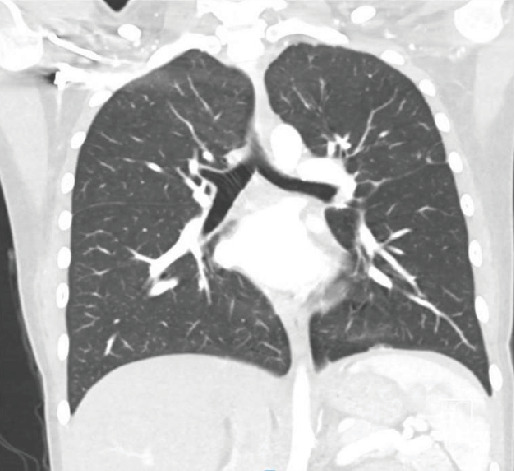

原发性纵隔大b细胞淋巴瘤(PMBCL)是一种高度侵袭性的恶性肿瘤,主要见于30岁左右的女性患者。这种罕见疾病的发病率为百万分之0.4,传统上表现为B型症状或压迫性后遗症,如SVC综合征或呼吸窘迫。在本报告中,我们报告了一位年轻女性的病例,她表现为心悸和心动过速,没有心肺按压症状,诊断为位于左心室的16厘米浸润性PMBCL。

Primary mediastinal large B-cell lymphoma (PMBCL) is a highly aggressive malignancy primarily observed in female patients during their third decade of life. This rare condition, with an incidence of 0.4 per million, traditionally presents with B symptoms or compressive-based sequela such as SVC syndrome or respiratory distress. In this report, we present the case of a young female who presented for palpitations and tachycardia without cardiopulmonary compressive-based symptoms diagnosed with a large 16-cm infiltrative PMBCL localized in the left ventricle.